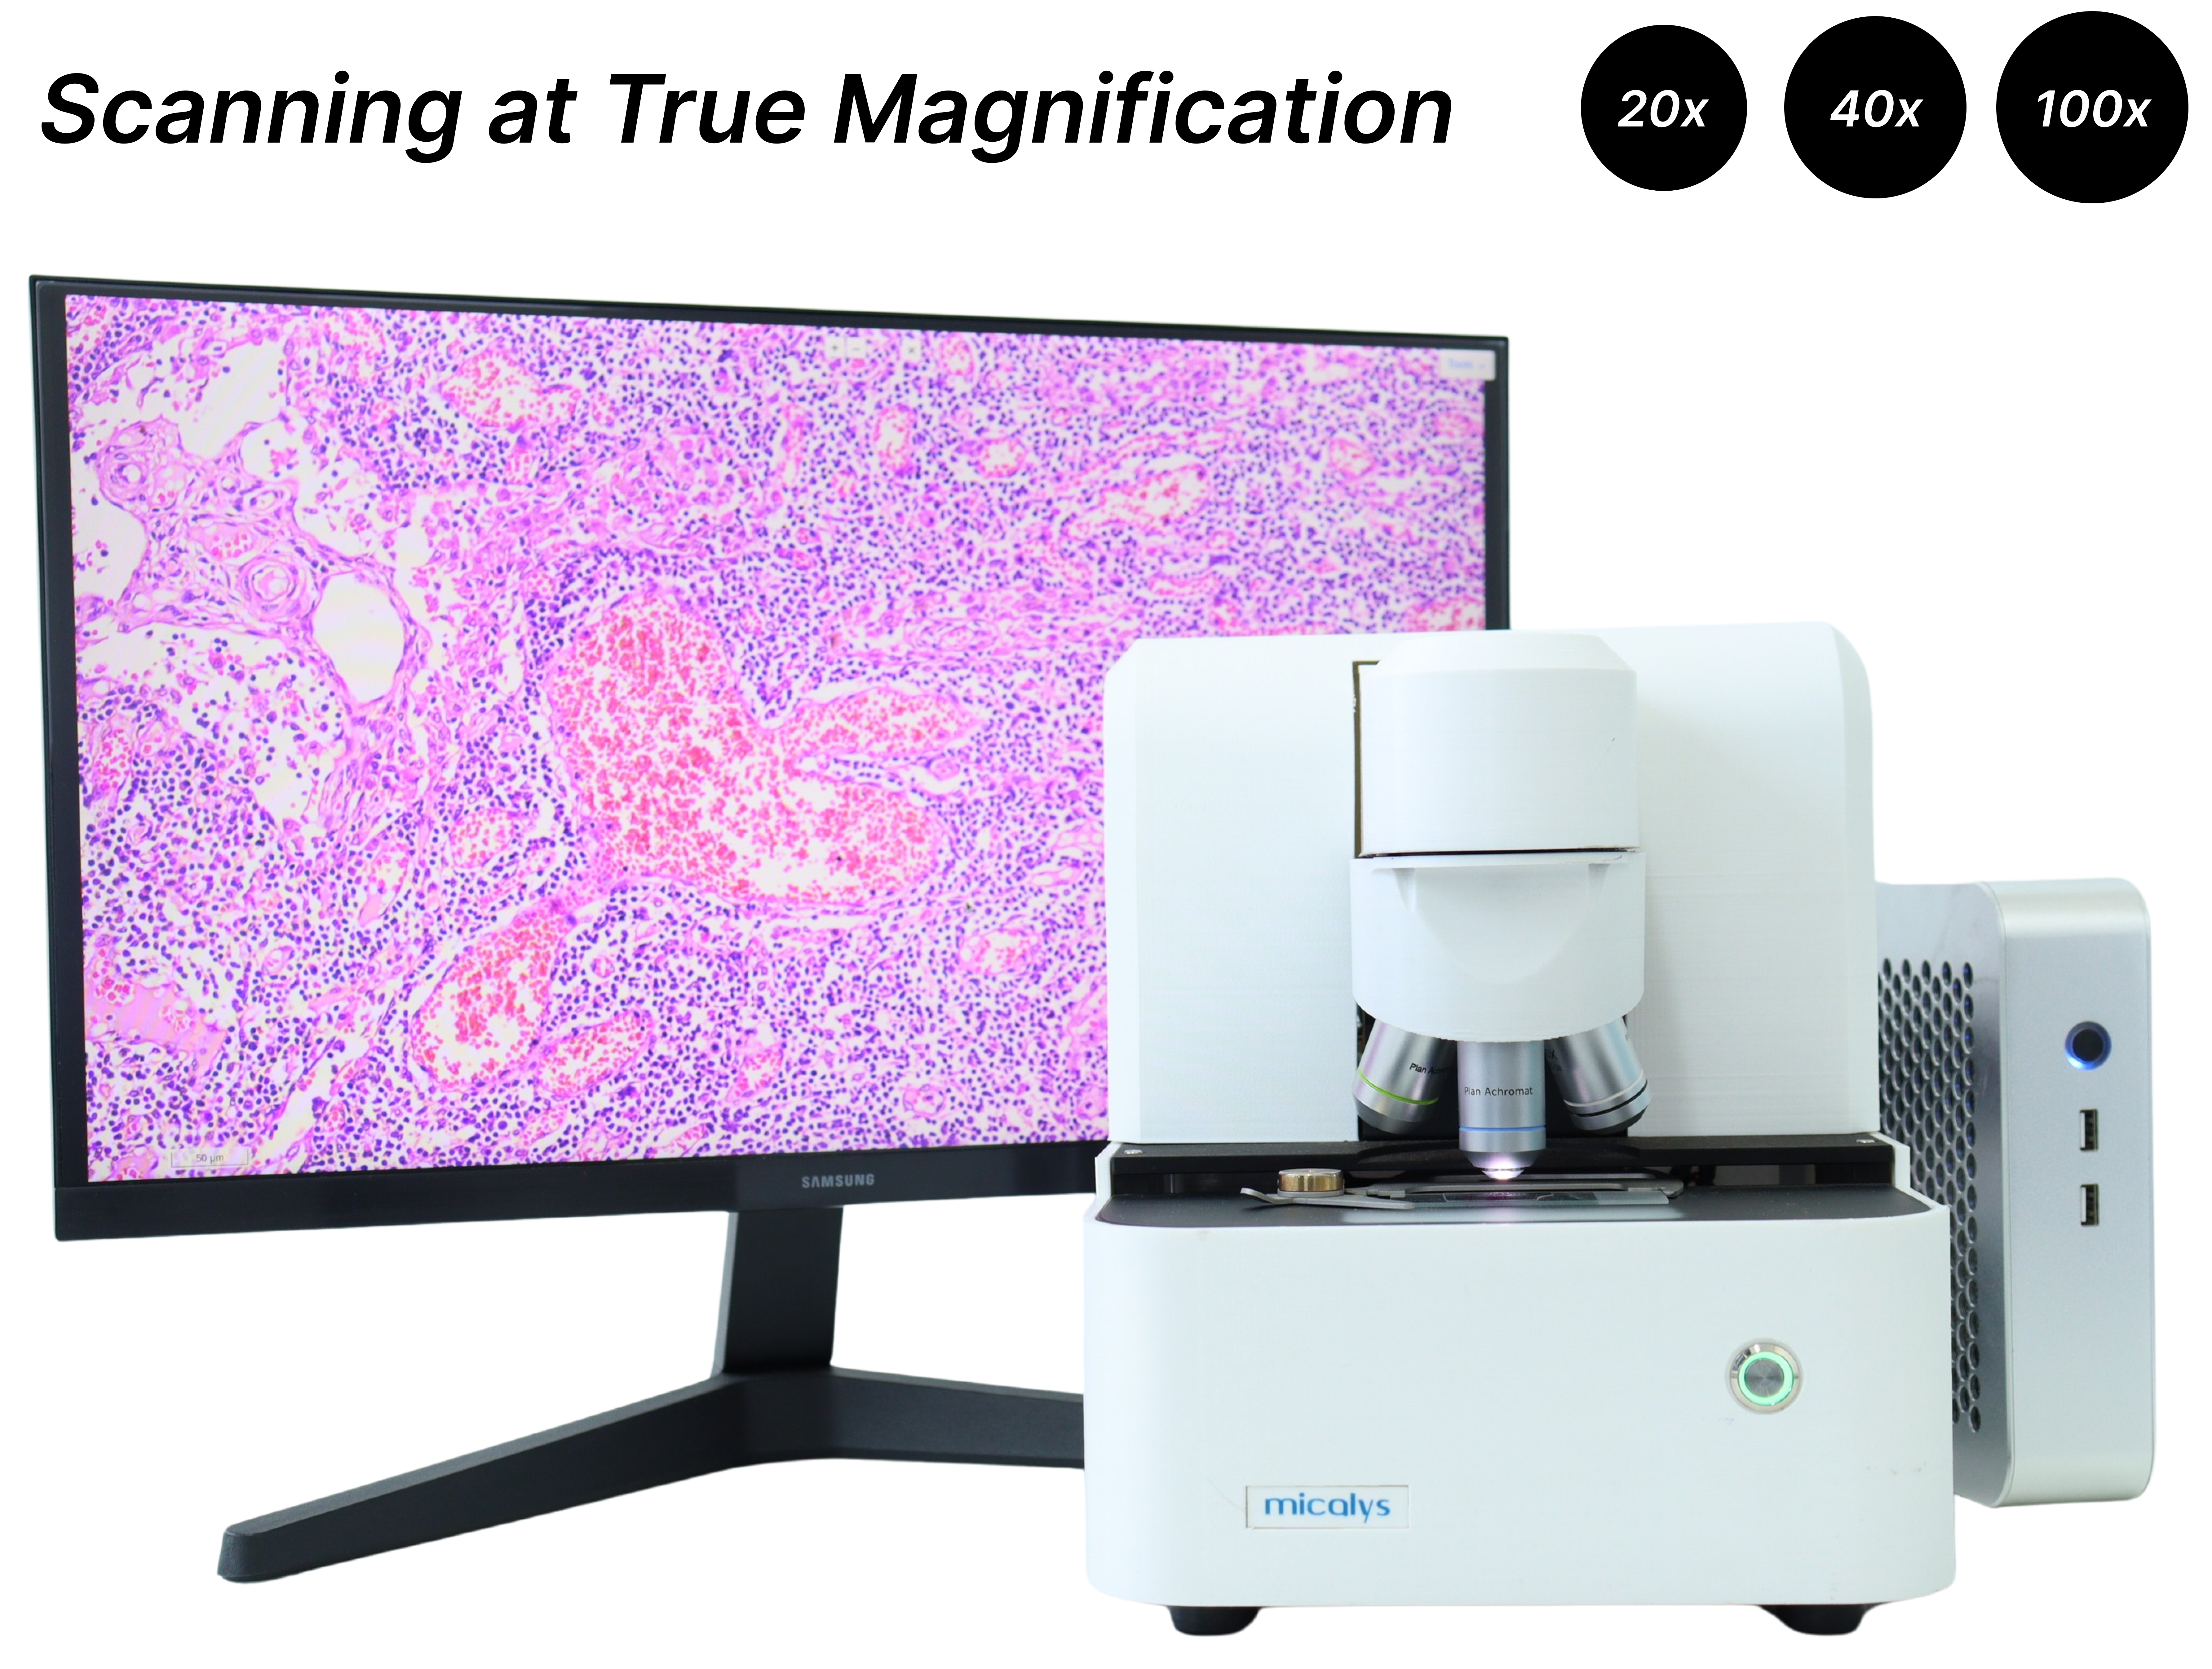

A multifunctional microscopy platform

Whole slide imaging | Telepathology | AI Assisted | Digital Microscopy

Micalys has unlocked all possible modes of microscopy to provide you with Integrated Microscopy experience

Whole Slide Imaging

High resolution imaging with just one click powered by intelligent area selection for a seamless process

Quick scan at a true 40x magnification with enriched visualization and secured sharing

True 100x oil immersion scanning available

High Quality Image

Outstanding image quality for various sample types including Histopathology, Cytology, PBS etc

Achieve high quality images of resolution up to 0.19 μm/pix at true 40x